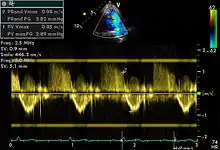

Spectral doppler

Spectral doppler is presented similarly to M-mode in which the doppler information is plotted as a spectrogram. This can be both "continuous" and "pulse" wave where the former shows the spectrum along a specific line and the latter shows within a small window along that line. Continuous wave is better at showing maximal velocities and pulse wave is better for showing flow through a small volume.

Spectral doppler is often used for quantification of flow. For example, the aortic valve area can be estimated using the continuity equation by measuring the velocity time integral (VTI) of the aortic valve & LV outflow tract; the VTI is calculated by tracing the flow on the spectral doppler curve. Spectral doppler is also useful for calculating the maximum flow and mean flow through a valve (used to grade valve stenosis).